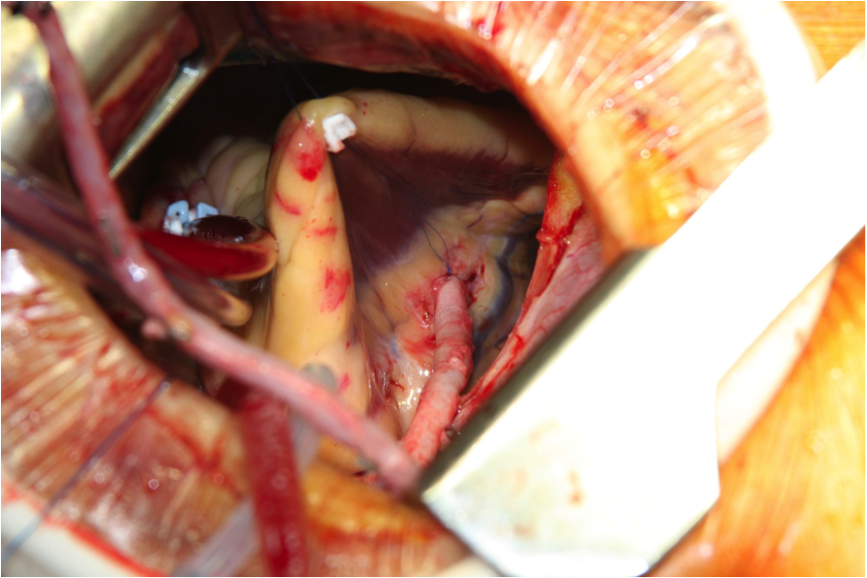

Figure 1: Following suspension of the RV acute margin. The visibility and access to the RCA through the right minithoracotomy is unobstructed and easy.

Femoral cannulation was carried out using 20 Fr arterial and 22 Fr venous multistage cannulas. A right minithoracotomy measuring 6 cm was performed, with an anterior orientation, reaching from the anterior axillary line to the mid-clavicular line. Following exposure, as described by Glauber, the aorta was cross-clamped using the Chitwood clamp and custodiol cardioplegia was given (1). Core temperature was maintained at 32 degrees C. The left atrium was opened and the main bulk of the LA mass (a myxoma, confirmed by histology) was removed under meticulous suction. The stalk was broadly based and was excised along with a 5x10 mm piece of interatrial septum at its base. The defect was closed primarily. Next, the atriotomy was closed using 3.0 Prolene suture. The acute margin of the RV was suspended on a pledgeted 4-0 Prolene suture and pulled towards the work-incision and then out. This helped to lift the RV very comfortably, and provided excellent access to the entire length of the RCA and posterior descending artery (PDA). A 15 cm saphenous vein was previously harvested in an endoscopic fashion. The authors proceeded with the distal anastomosis first, using 7-0 Prolene, followed by the proximal anastomosis on the still-arrested heart and cross-clamped aorta. Following re-warming, the heart was de-aired both through the LA (vent) and the aorta (punched aortic orifice for the graft anastomosis), the cross-clamp was released, and the suture completed. The heart resumed immediate sinus rhythm and good contractility. The saphenous graft flow was measured to be over 60 ml/min via MiraQ™ Cardiac (Medistim, Norway). On intraoperative, post-procedural echocardiography there was no ASD and good ubiquitous contractility. The total cross-clamp time was 75 minutes.